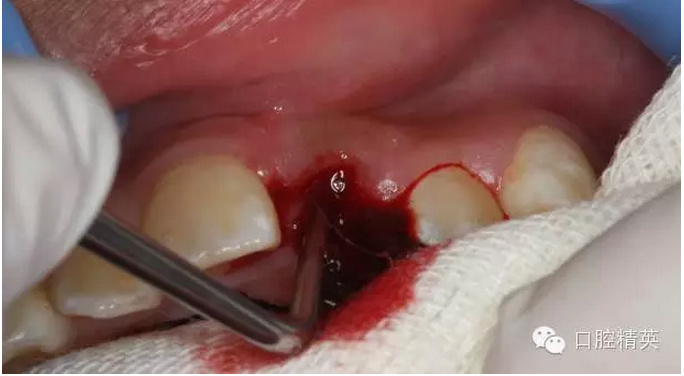

圖13.清理21牙槽窩

圖2.口內(nèi)整體影像